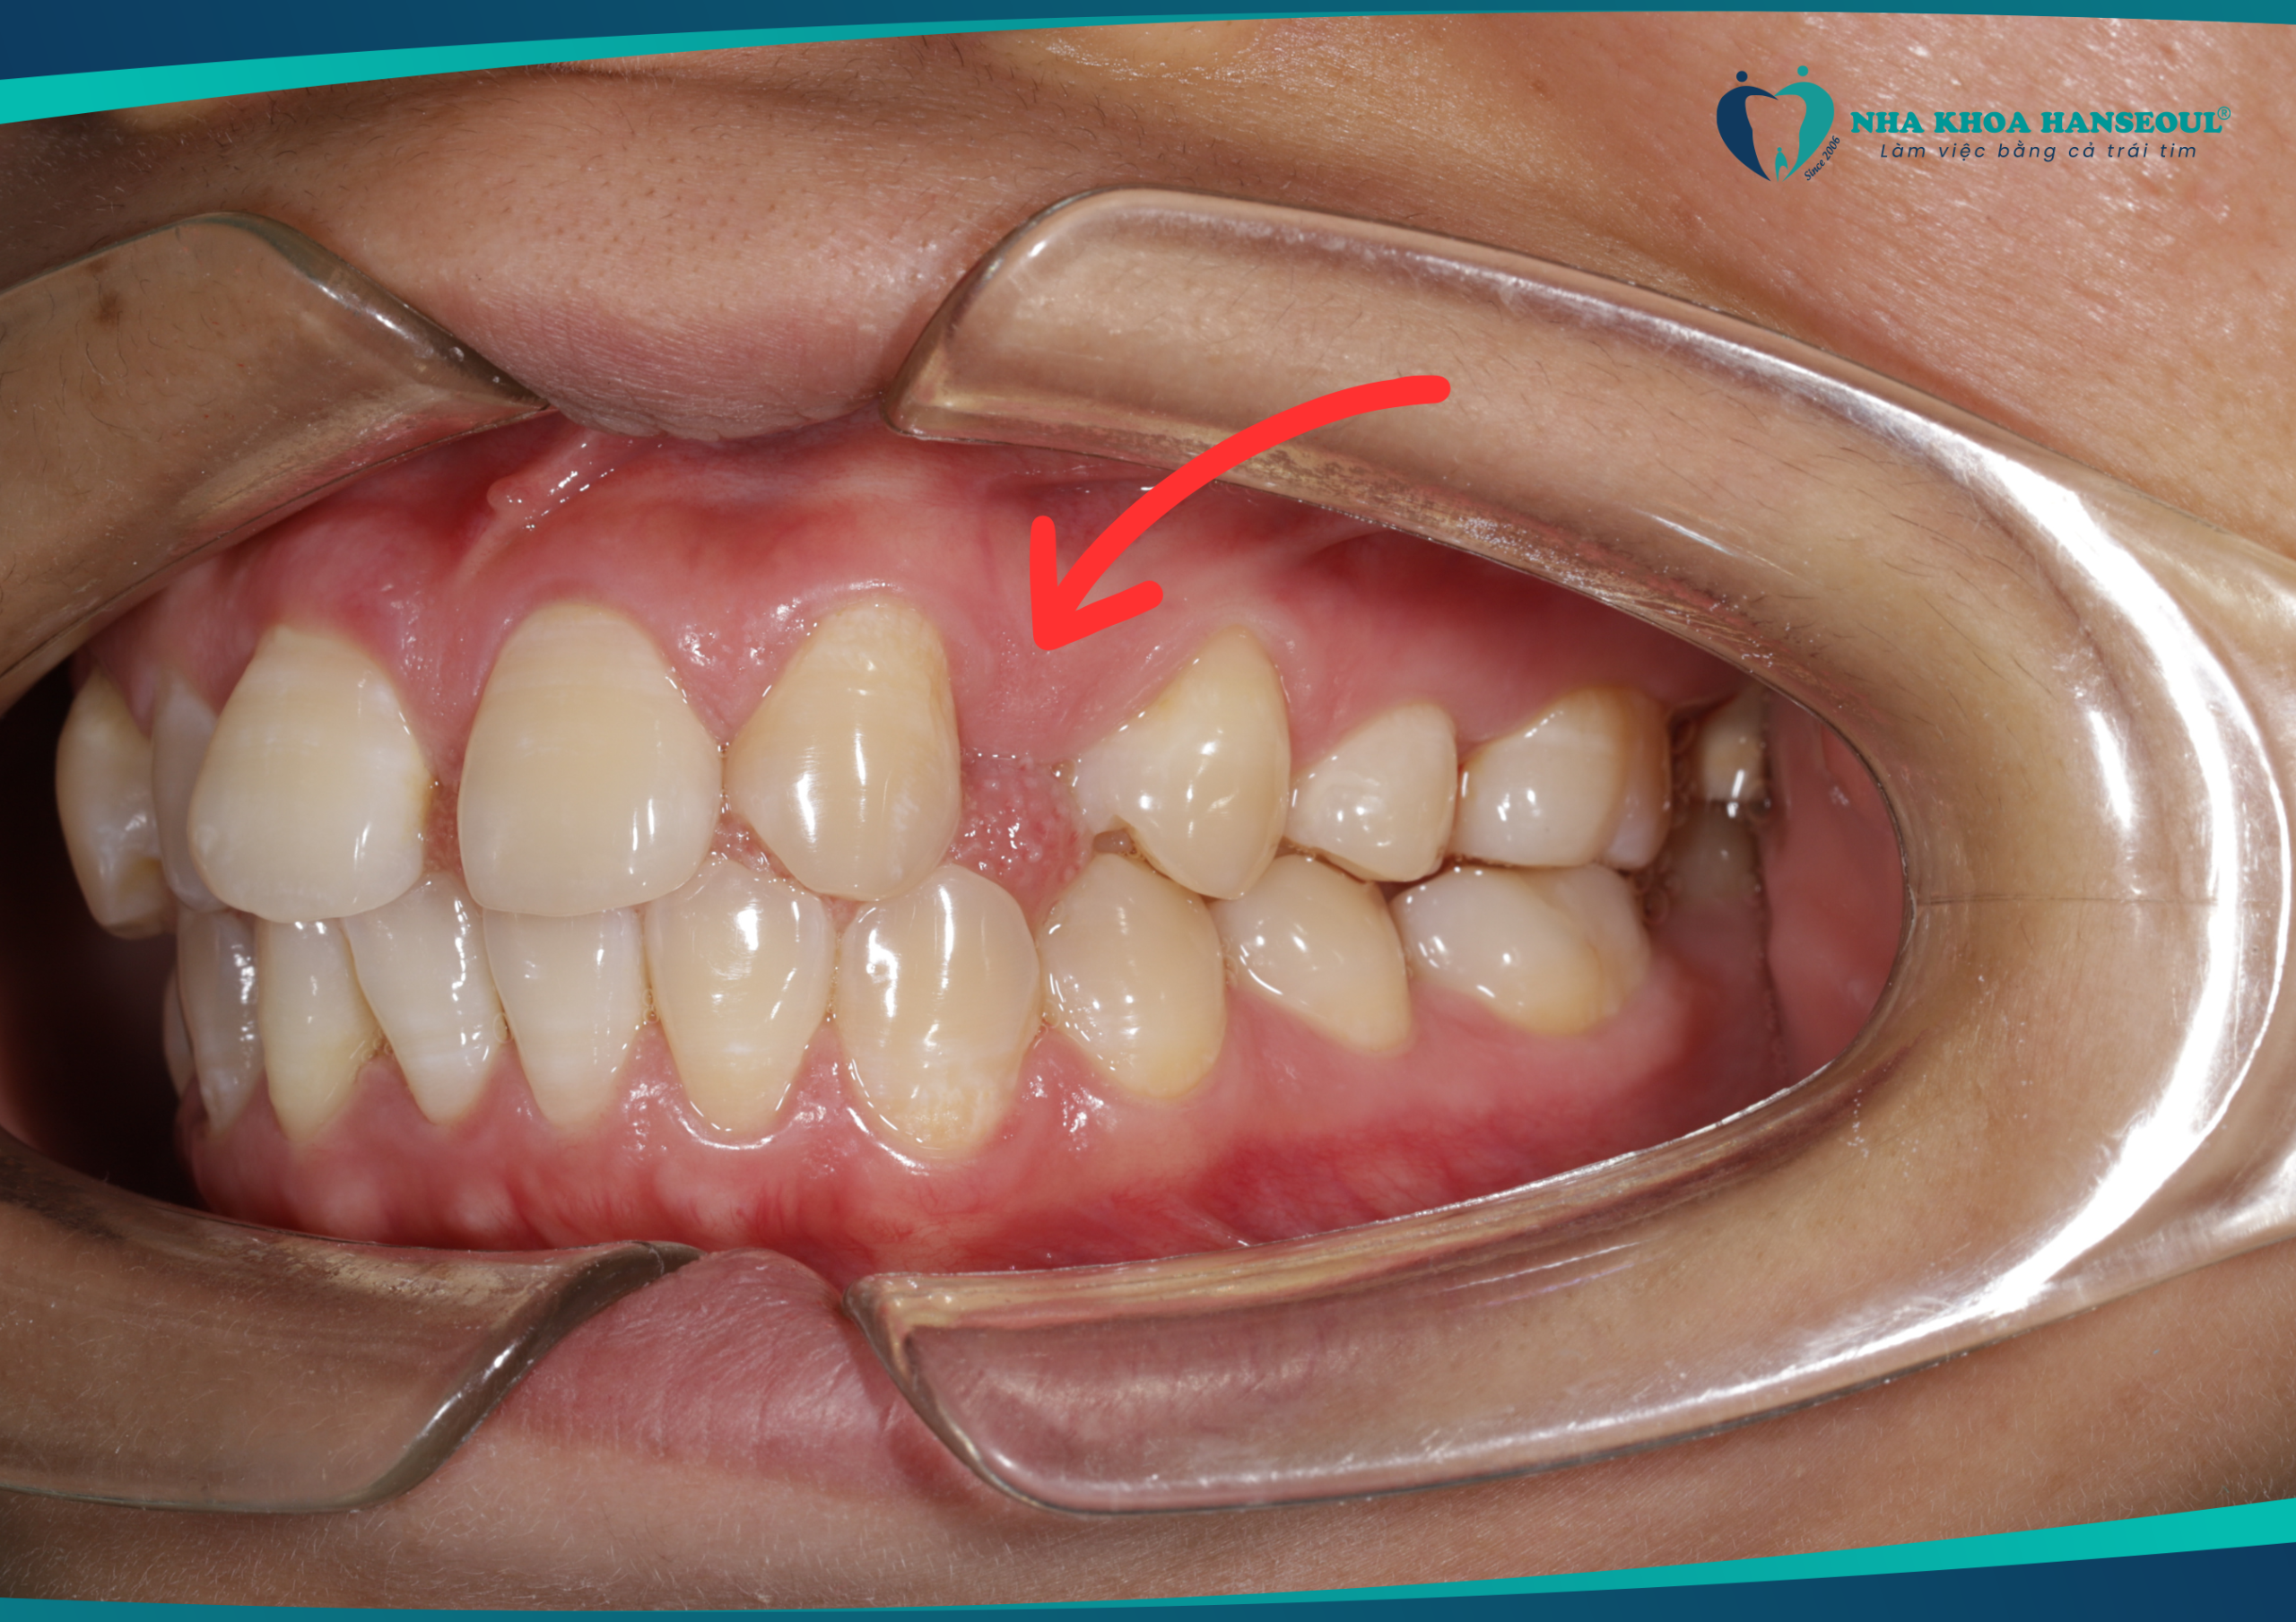

Tình trạng răng cửa thưa và mất một răng trước điều trị của chị Mị